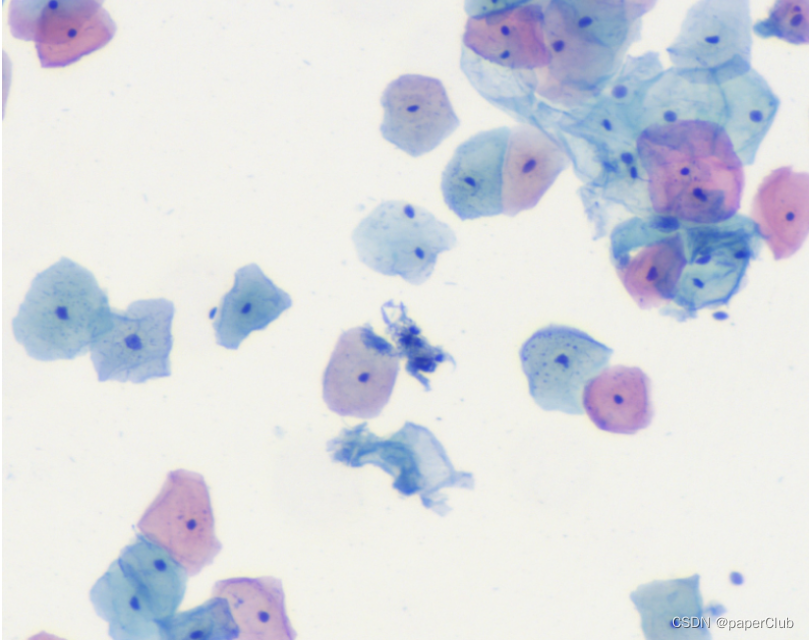

- 生物细胞图像

如图,动物细胞主要由细胞质(浅蓝色或浅红色)和细胞核(深蓝色)构成。我们看到的生物细胞颜色会有所不同,有浅蓝色的和浅红色的,颜色不同是由于细胞质和染色液结合后发生了不同的显色反应(主要是由于细胞内环境及PH差异引起),这也反应了细胞所处的阶段或生理转态不同,中间的深蓝色小点就是细胞核。